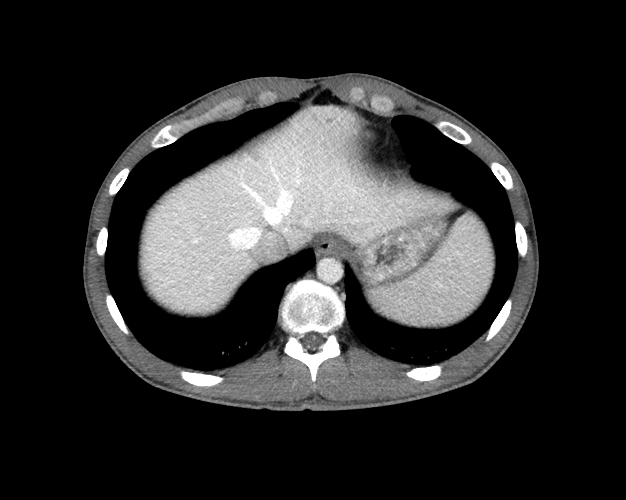

Body

Covers abdominal CT anatomy.